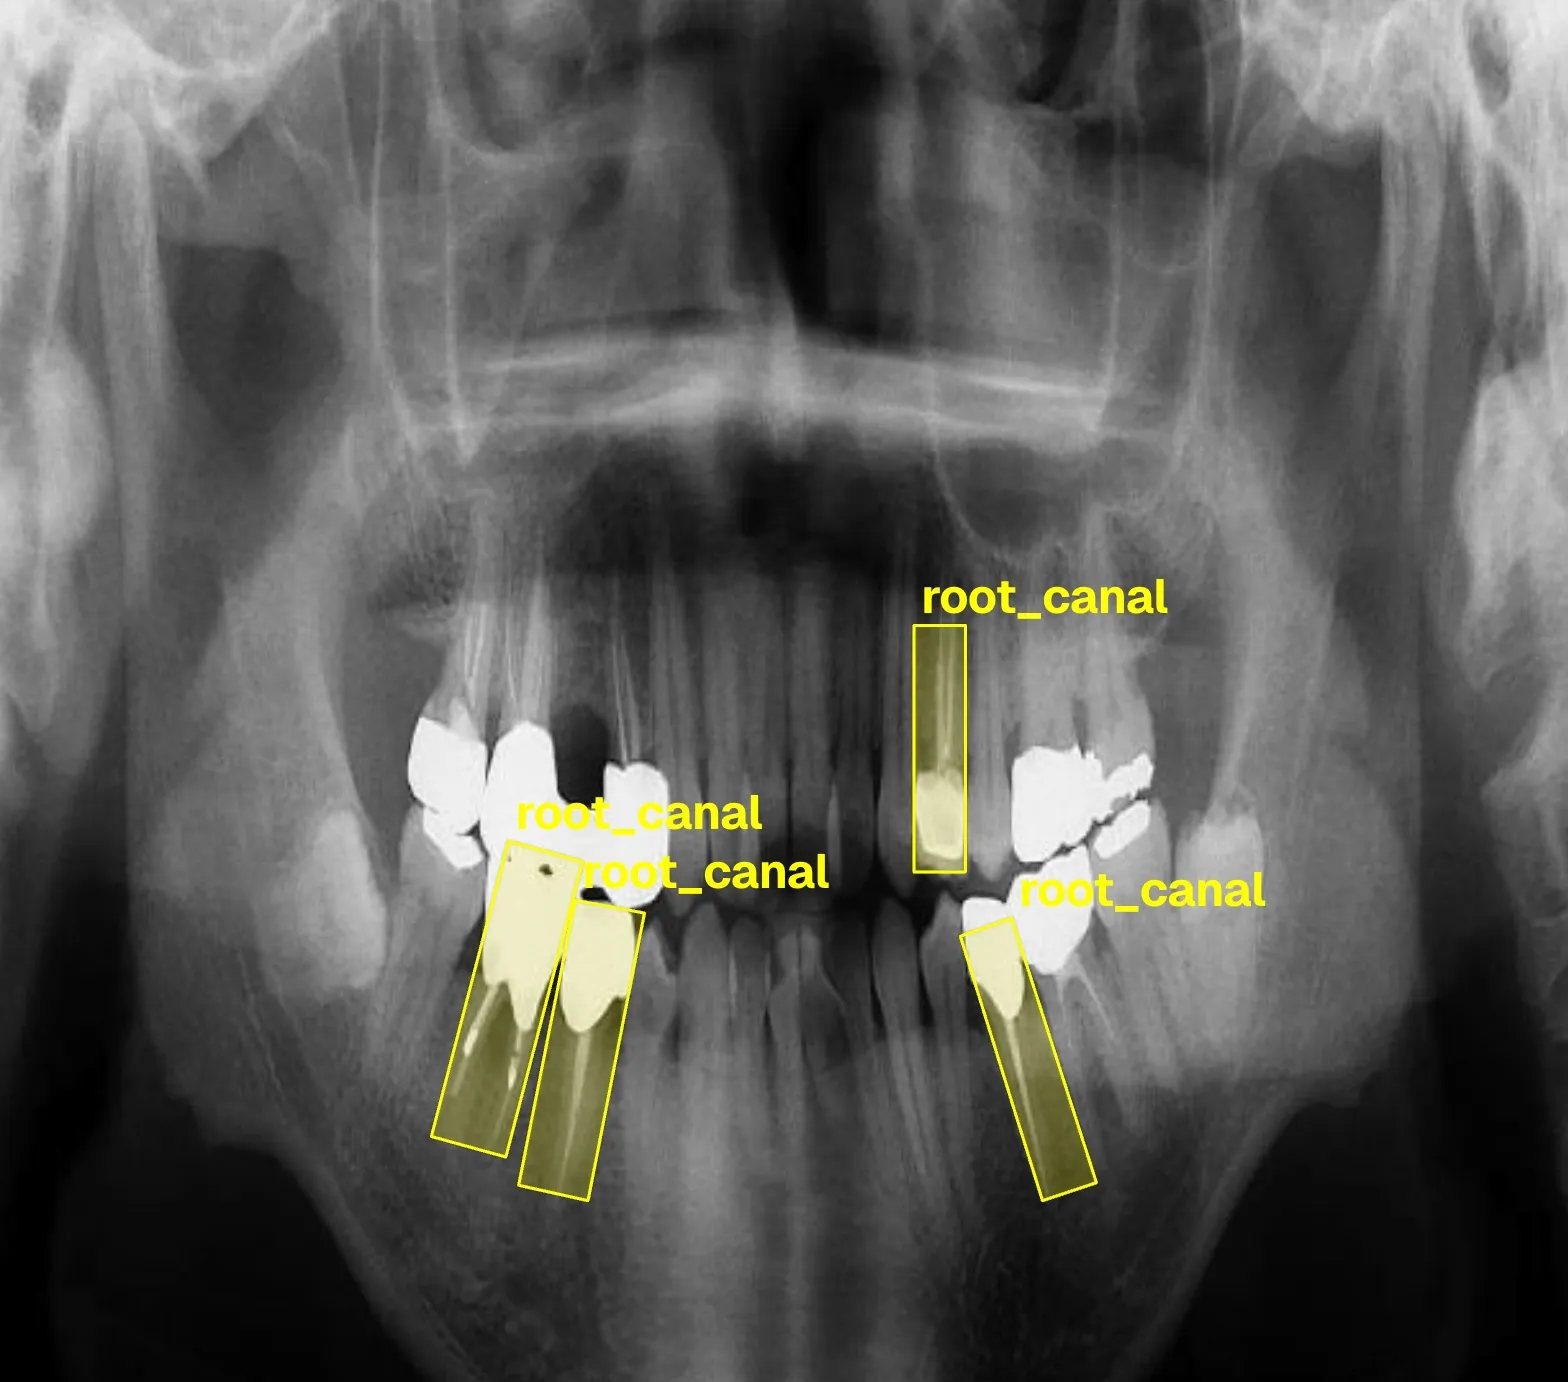

Building computer vision datasets and training YOLO models for automated dental pathology detection on panoramic X-rays.

- Root canal therapy guiding RCT dataset annotations

Annotating dental X-rays with clinician-grade precision for object detection and OBB tasks.

Training and publishing YOLO-based detection models for dental diagnostics on Ultralytics Hub.